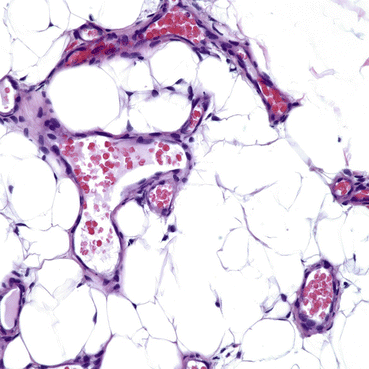

Fig. 8.6

Note the prominent spindle-shaped pericytes in aggregates. The endothelial spaces are scattered amidst these aggregates, and exhibit plump luminal cells. Note the numerous mitoses represented by dark oval, round, and rectangular-shaped structures. There are scattered mast cells and lymphocytes throughout the cellular population